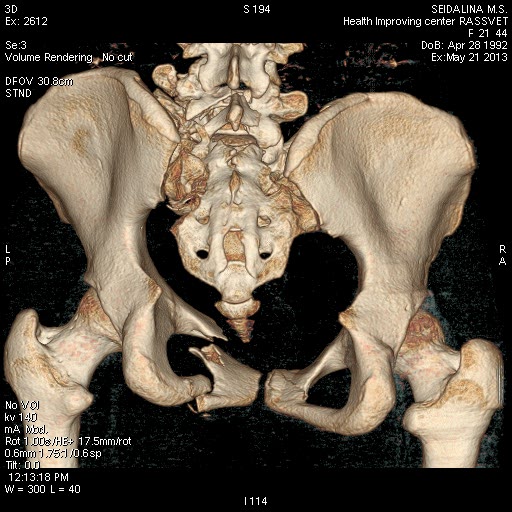

Сегодня мы имеем вот такой таз!Девушка 23г .Укорочение 4 см.

Давность травмы 5 нед, остеосинтез проведен к концу второй недели. КТ не получается отправить на диске, хитрая программа - не копирует. Вся боковая масса крестца, где илиосакральные винты, в мелких осколках. Перелом поперечного отростка 5 поясничного позвонка, в него так и упирается крыло. Неврологии нет.

КТ до операции.